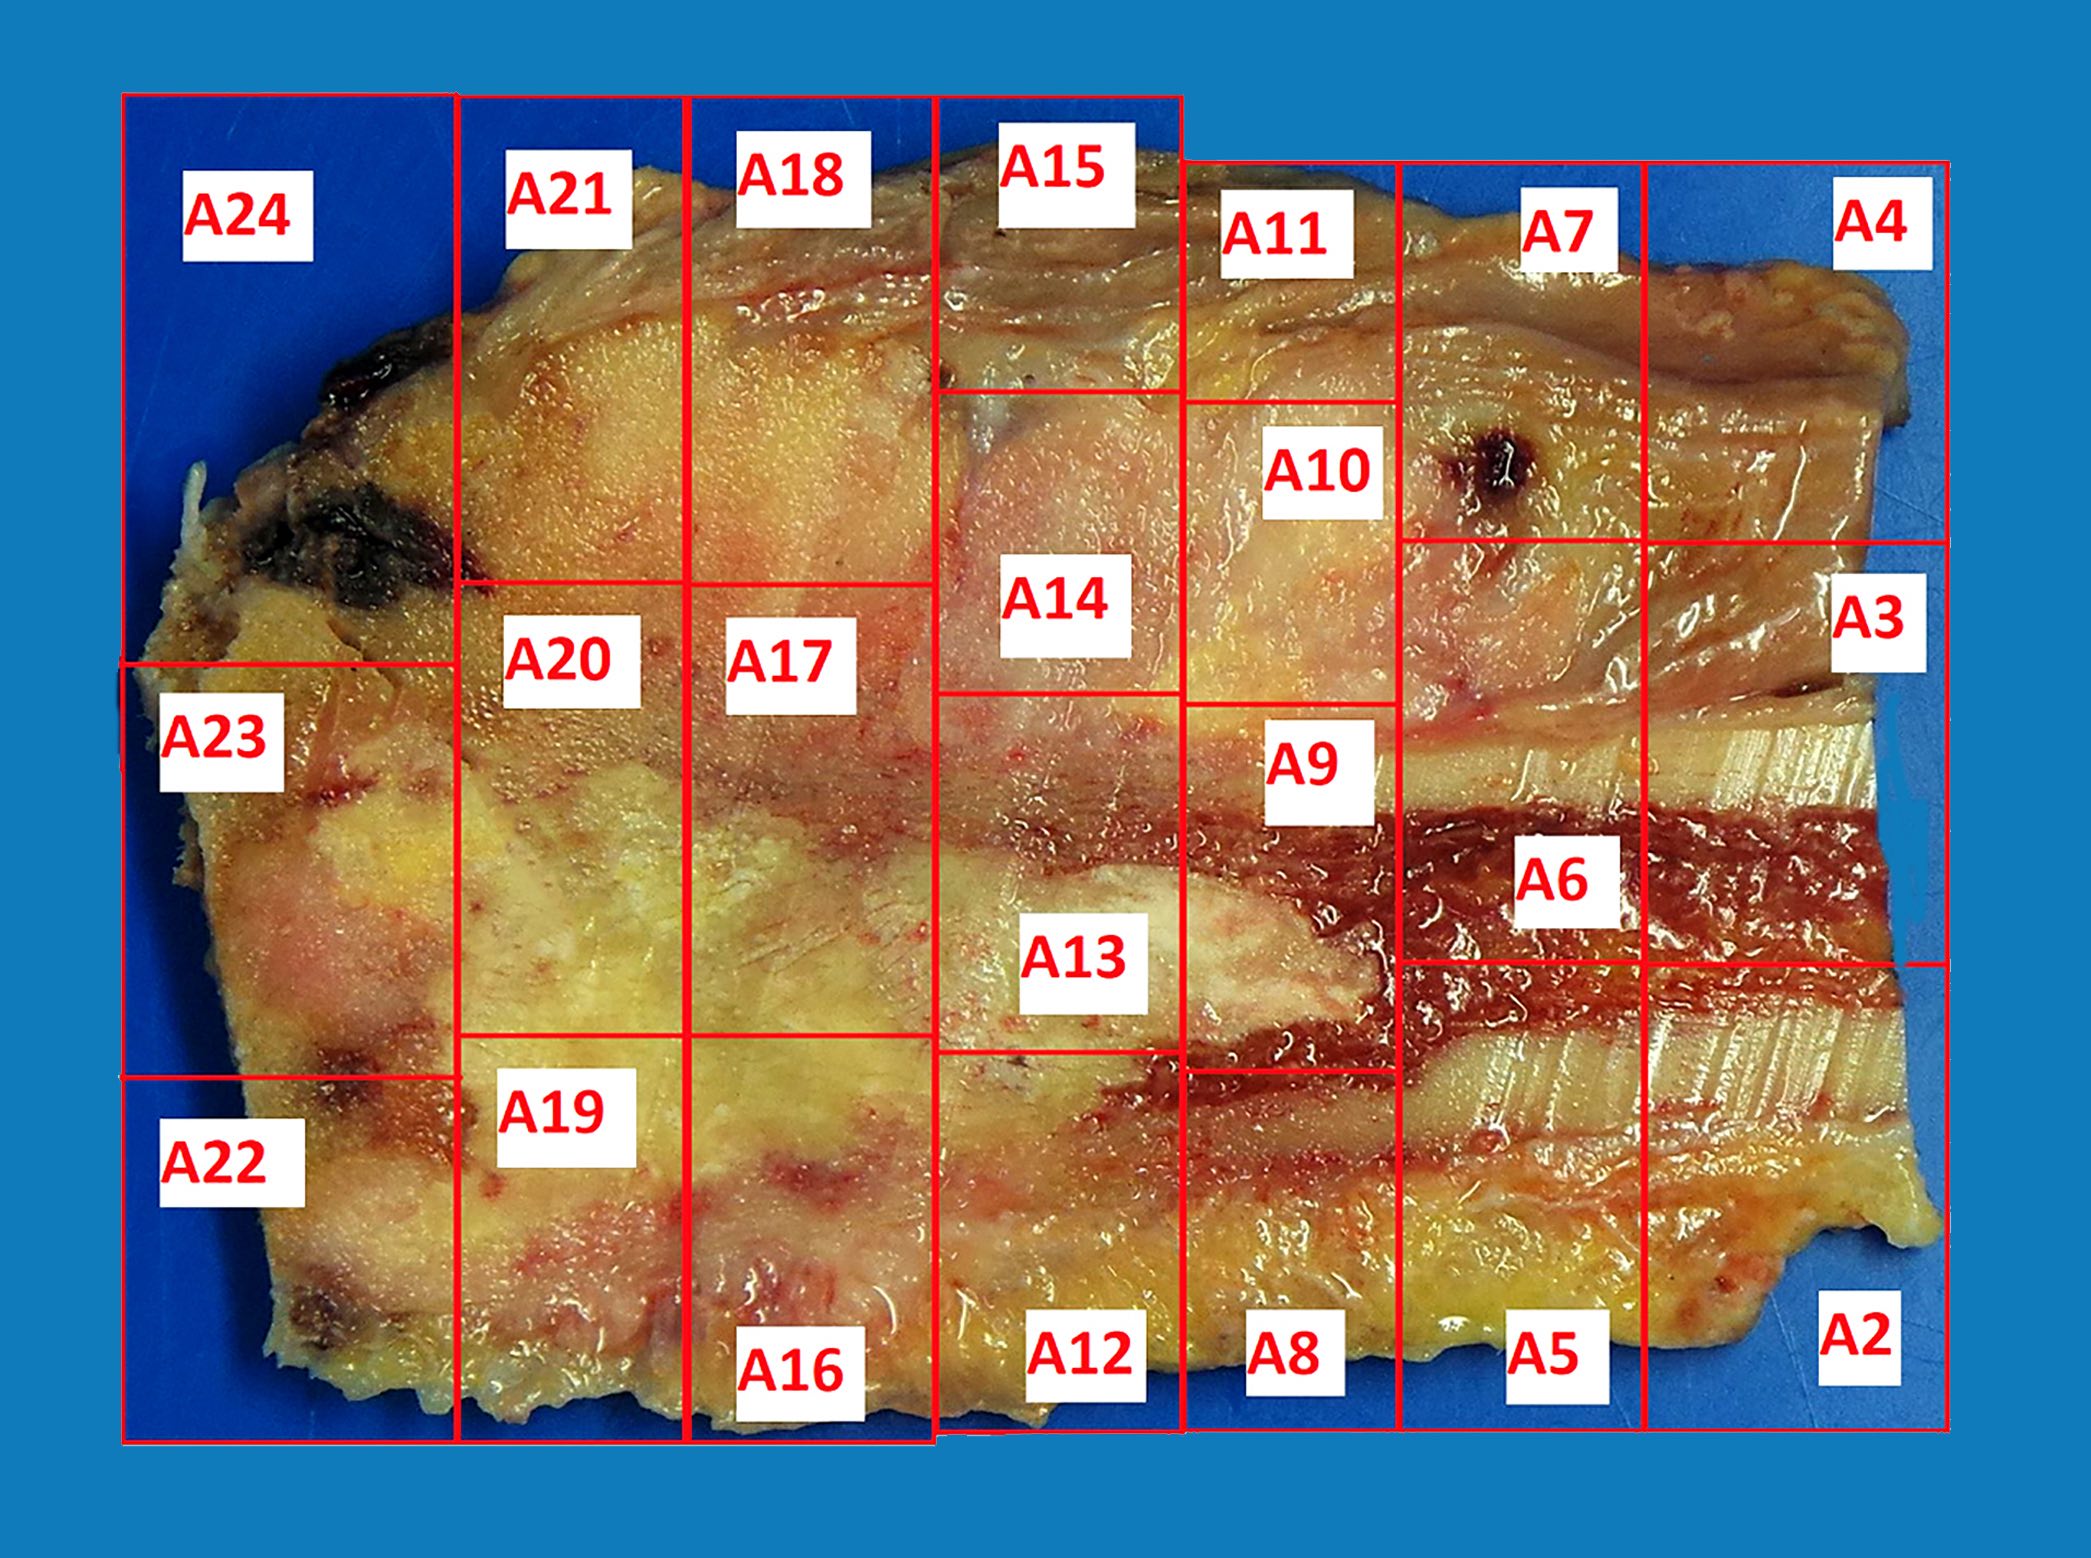

- Assessment of preoperative chemotherapy:

- Preoperative chemotherapy is commonly used with limb salvage procedures for treatment of high grade sarcomas, particularly osteosarcoma and Ewing sarcoma

- It is generally required to quantify the extent of tumor necrosis as a percentage of the total tumor area

- For osteosarcomas, chemotherapy induced necrosis of ≥ 90% has a > 90% disease free survival, compared with < 50% in patients with < 90% tumor necrosis

- To determine the extent of necrosis in an osteosarcoma or Ewing sarcoma specimen, the slab specimen of the resected bone containing tumor provides the template for histologic analysis

- Photograph of the slice is taken and the site of each numbered block is marked on a grid pattern diagram

- Status postneoadjuvant chemotherapy:

- To gross: cut along long axis of tumor and map

- Status postneoadjuvant chemotherapy:

- Report treatment response as a percent tumor necrosis (really an assessment of tumor drop out)

- Edematous scar: loose edematous to myxoid granulation tissue, fibrosis, mild chronic inflammation

- Bony matrix remains

- Residual tumor cells: nests of tumor cells in retraction clefts are common

- Grading response to chemotherapy (same cutoffs as Ewing sarcoma) (Cancer 1993;72:3227, J Clin Oncol 1988;6:329):

- Good response is > 90% tumor necrosis

- Report treatment response as a percent tumor necrosis (really an assessment of tumor drop out)